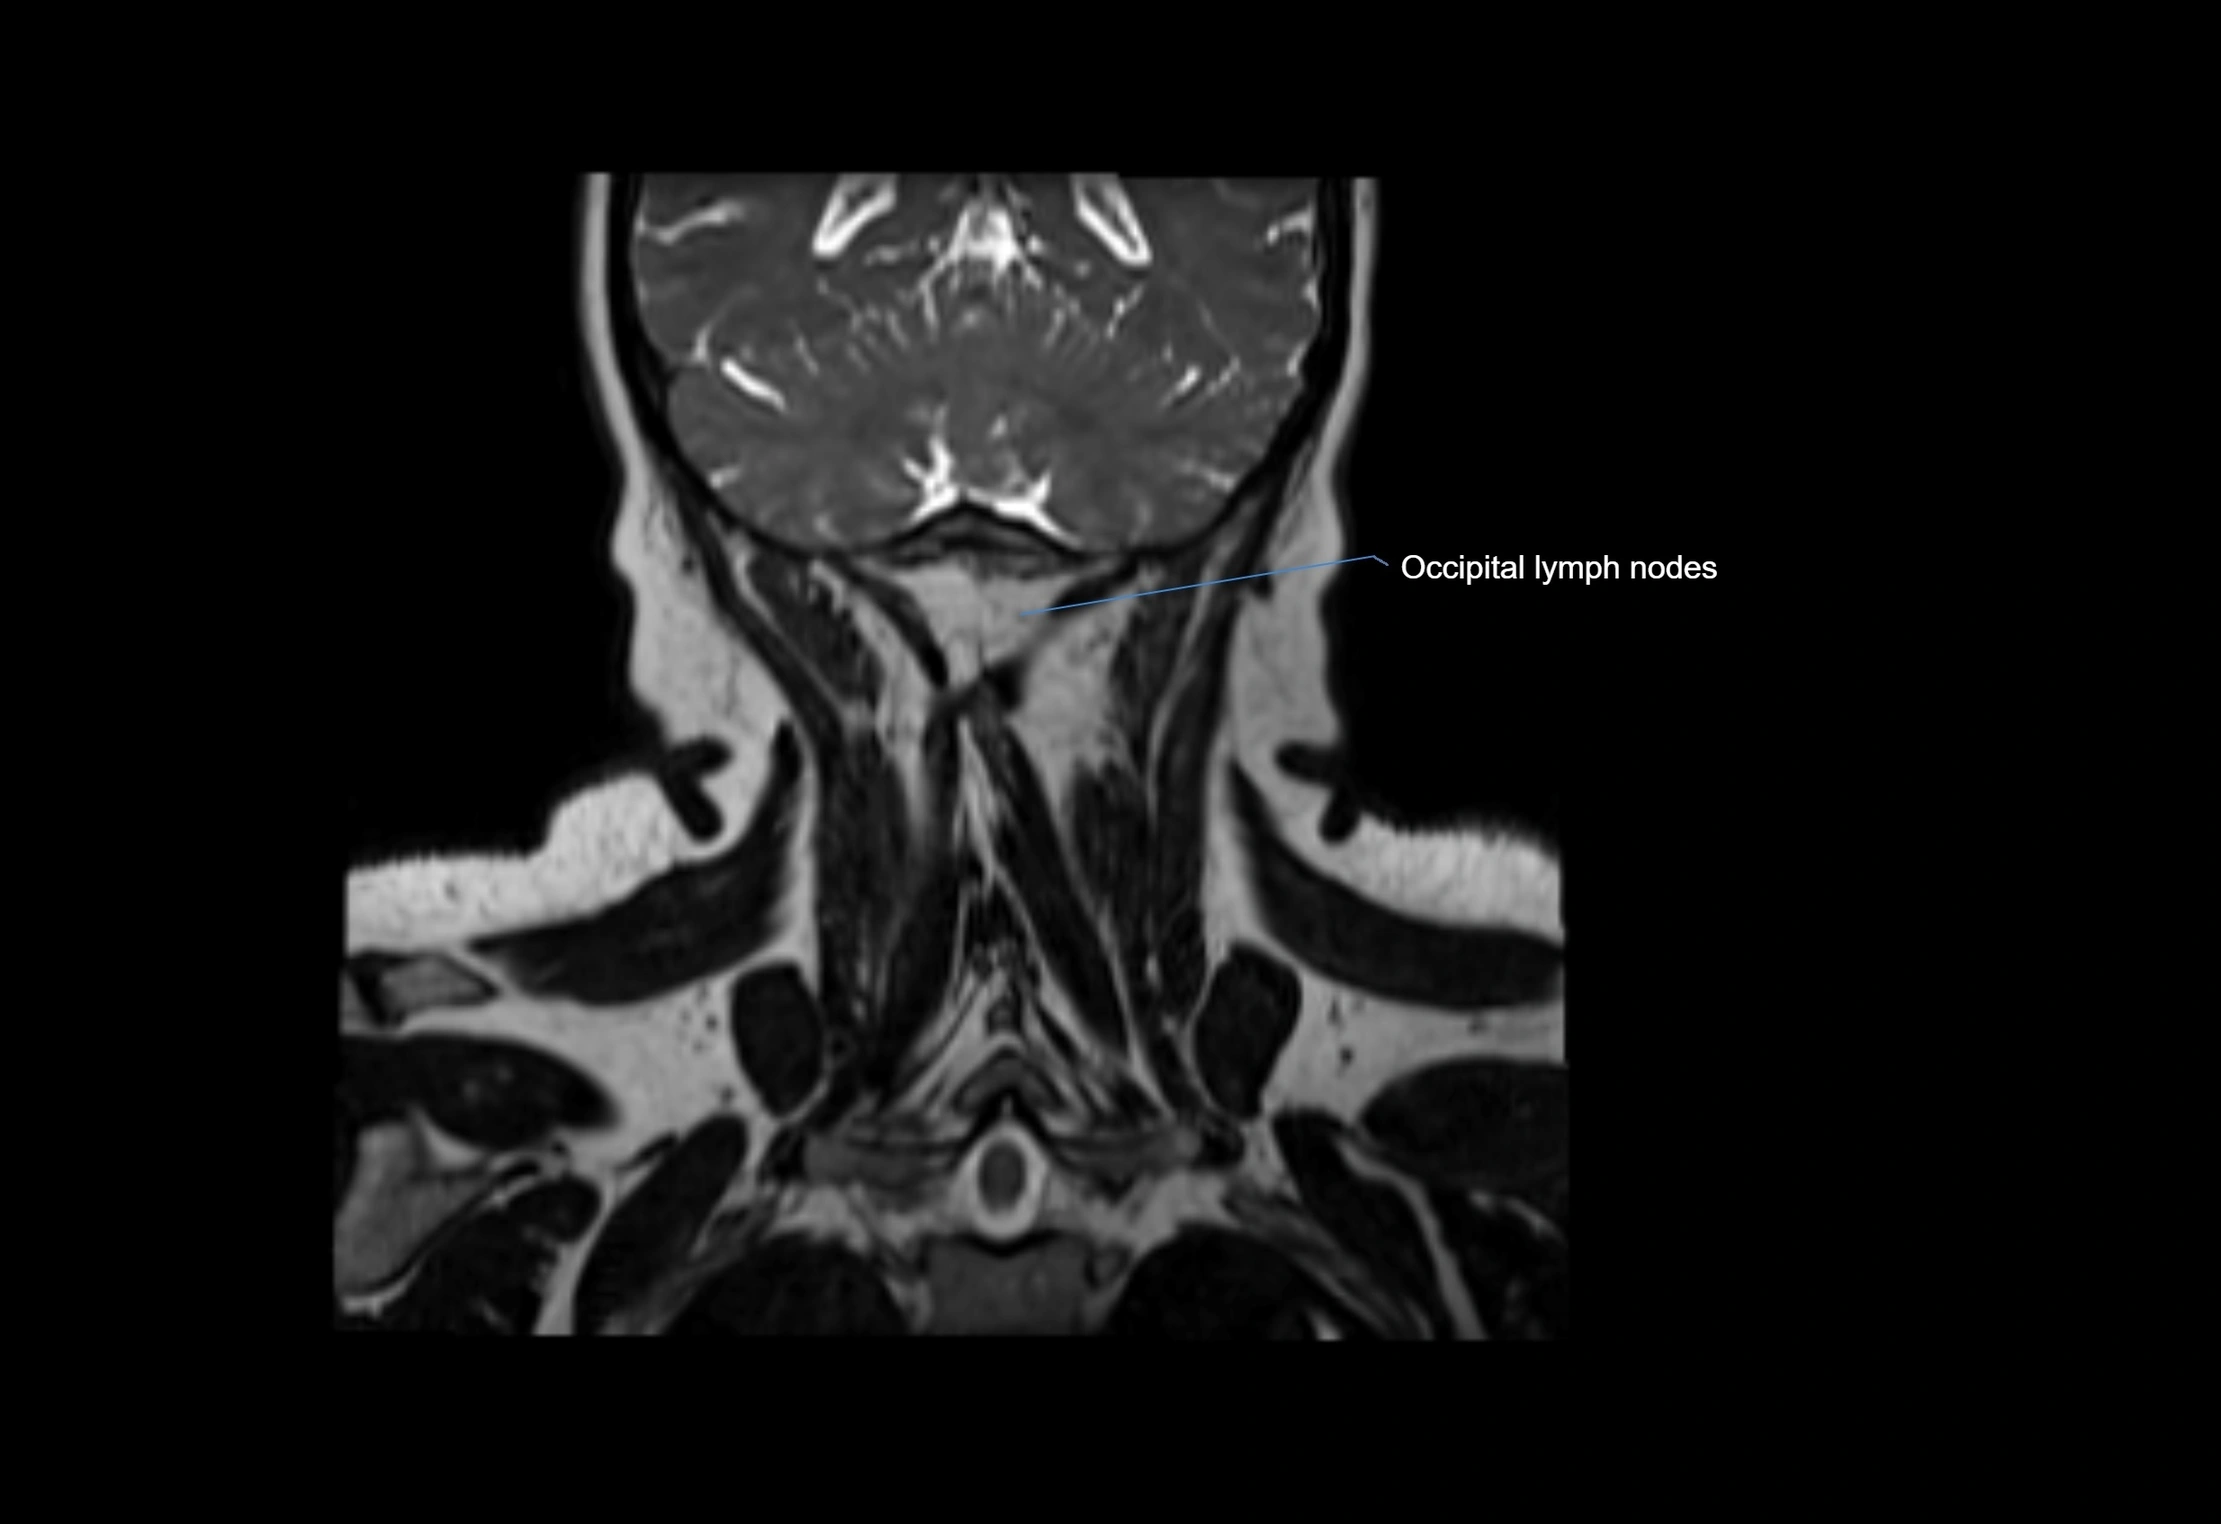

Location

• Found along primary lymph node chains, including preauricular, submandibular, parotid, and occipital regions

• Embedded in subcutaneous fat or superficial fascia, often lateral or posterior to primary nodes

• Variable in number; may occur unilaterally or bilaterally, depending on individual anatomy

MRI images

image